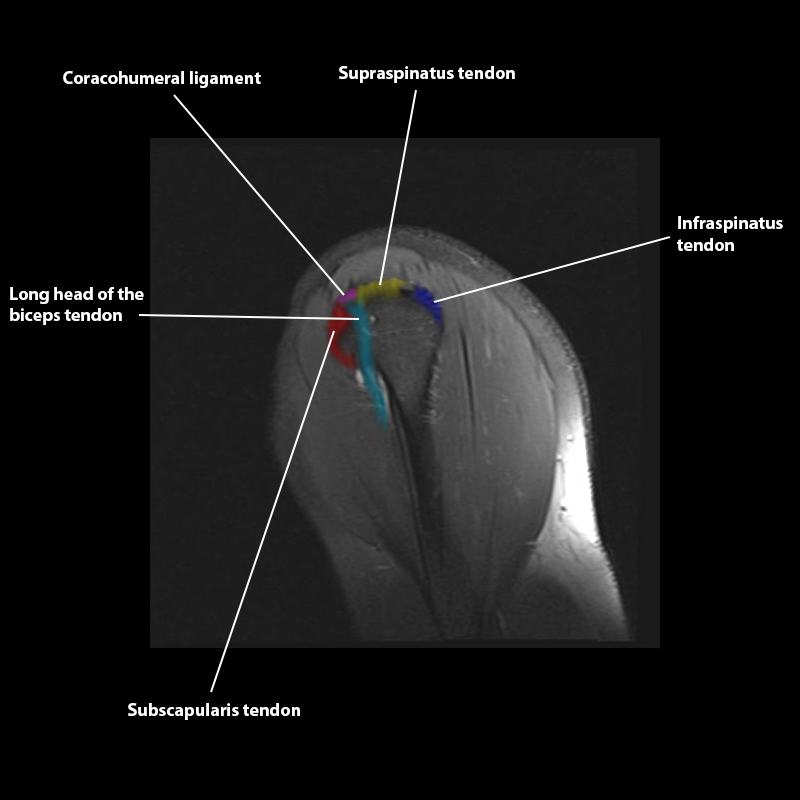

Shoulder MRI Anatomy